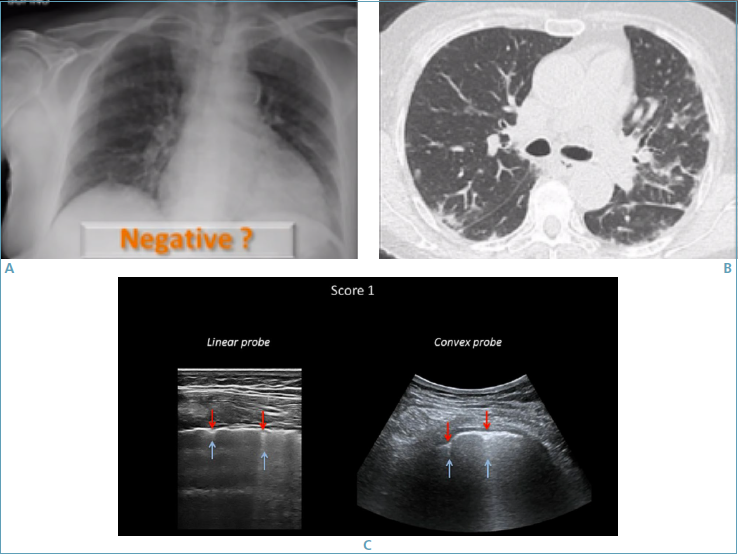

L’ecografia del torace si è dimostrata particolarmente utile nella diagnosi precoce dell’interessamento polmonare e per evitare la mobilizzazione del paziente, inoltre consente di effettuare un follow-up ravvicinato del parenchima polmonare e quindi di seguire l’evoluzione della polmonite anche al domicilio del paziente 33,34 (Figg. 4, 5).

All’esordio sono visibili rari artefatti verticali (linee B) ed una irregolarità e frammentazione della linea pleurica (Fig. 4), in seguito compare la classica sindrome interstiziale pneumogenica con numerosi artefatti o linee B che cominciano a diventare confluenti ed evolvere nel cosiddetto polmone bianco (linee B per una quota maggiore del 50% dello schermo), espressione di aree di compattazione parenchimale millimetriche non aerate sub-pleuriche.

Figura 4.Valutazione della polmonite da COVID-19 con ecografa toracica 33. L’ecografia del torace può essere particolarmente utile nella diagnosi precoce dell’interessamento polmonare e per evitare la mobilizzazione del paziente. Infatti, nelle prime fasi della malattia polmonare, l’RX torace può essere negativo, dato che prevalgono le aree a vetro smerigliato che non sono facilmente visibili all’RX torace ma solamente alla TC del torace (A, B). In questa fase, all’ecografia del torace, possono essere visualizzate precoci alterazioni, ad esempio irregolarità della linea pleurica da cui si dipartono singoli artefatti verticali o linee B (C).